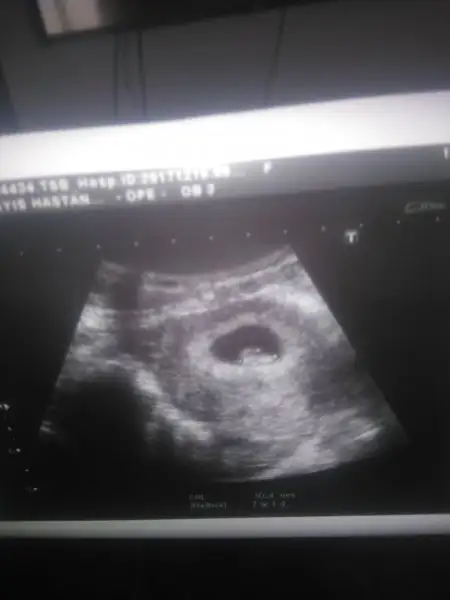

Bende pko var Cnm altı ay dur istiyorduk ovulasyon testiyle takip ettim günümü yumurtlama gününden bi gün önce ve sonra ilişki oldu öncesinde beş gün olmadı eşim yoktu ama ben le onla alakası yok tamamen nasip Cnm